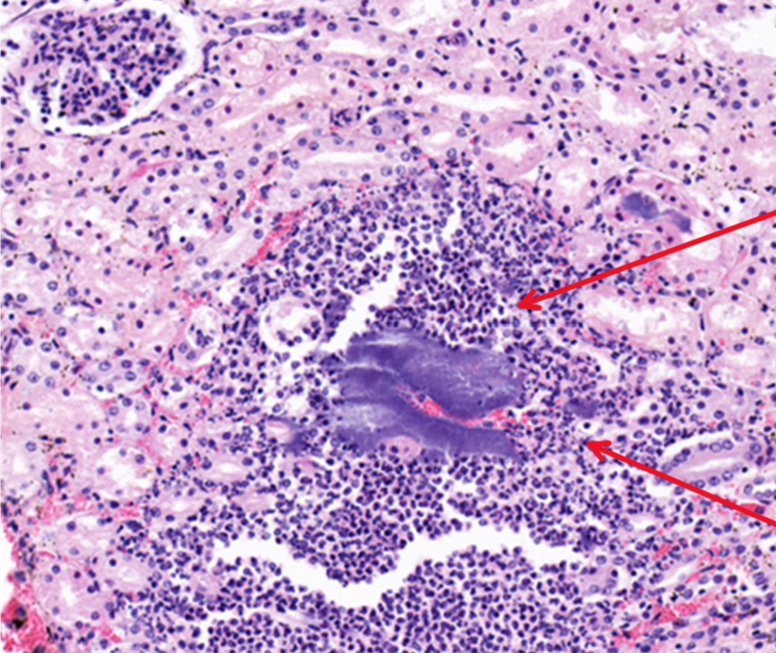

What are these cells and what does this imply about the duration?

A

neutrophils which suggests acute inflammation

There are bacterial colonies trapped and proliferating within the capillaries, are they post mortem or are they important in the pathogenesis of the lesions?

they are likely antemortem bacteria because they are surrounded by an inflammatory response

Q

What would the morphologic diagnosis for this lesion?

acute purulent glomerulonephritis with bacterial colonies

Identify this structure:

bacterial colonies

19

What is this an area of?

congestion

20

What is this?

fibinous thrombosis